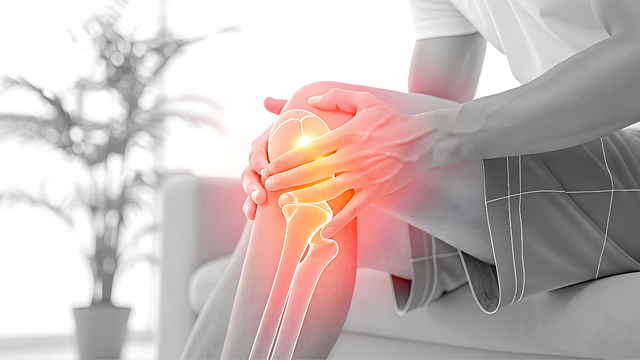

Rạn xương